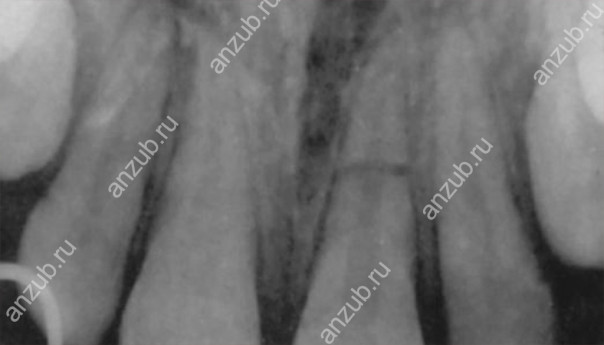

Наиболее информативным методом диагностики будет рентген или, лучше всего, компьютерная томография. С их помощью можно оценить не только место перелома и линию разлома, но и состояние окружающих тканей.